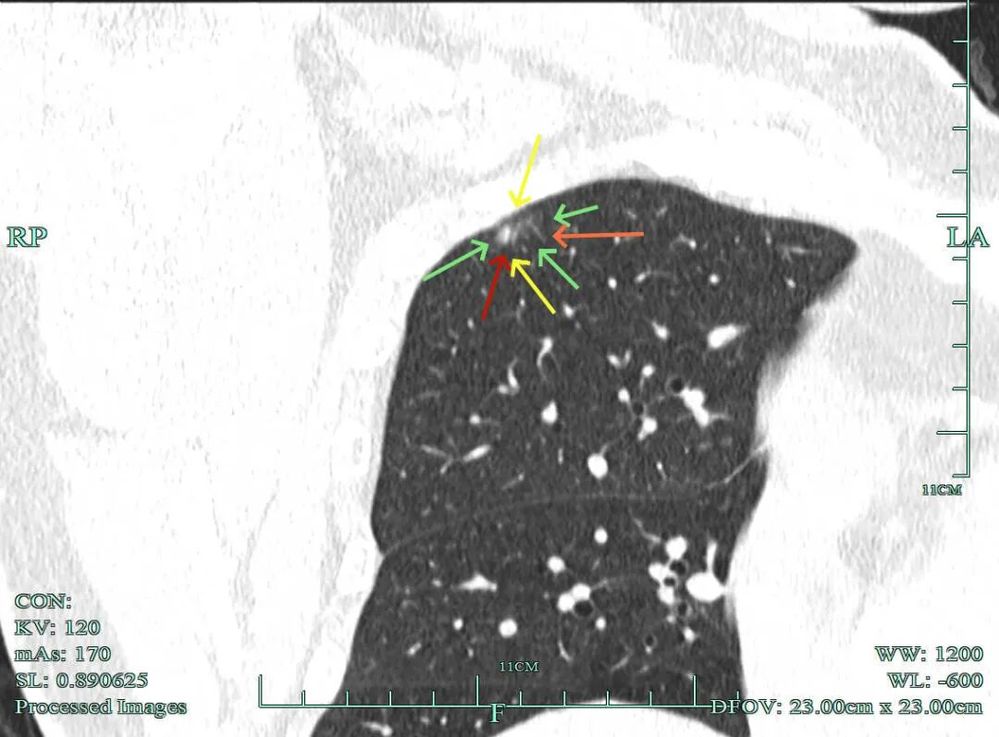

影像展示与分析:

杭州市肿瘤医院影像展示与分析:

右上也有混合密度结节,实性部分缺乏膨胀性与收缩力,磨玻璃成分较淡,也偏糊,但持续存在仍得考虑肿瘤范畴可能性大。

此视角是混合密度,实性为主,贴胸膜近。

今天这位结友的病理类型稍差于术前的预测,但从其三年多随访情况来看,进展不算大厉害,第10组与第12组淋巴结均阴性的话,还是真早期的可能性还是较大的。后续倾向暂随访观察,可以采取相对稍积极的随访策略,比如两年内4个月复查一次,三到五年内半年复查一次,五年后再年度复查;而且右侧的病灶要在随访进展或身体恢复良好后微创局部楔形切除。期间万一有转移,其实是伪早期的话,则基因检测并全身性治疗。其实今天这种病灶在临床中被判断为炎性的并不少见,尤其是非胸外科医生。因为胸外科的一般相对积极,警惕性高些。在我的公众号上其实也分享过多例这种看着似乎是炎性,但长时间随访不好转,或缓慢进展的病灶其实是浸润性腺癌的一种特殊表现,不少见的。我感觉此类病灶比较主要的临床特征是:1、密度多是混合磨玻璃密度,实性成分较明显,磨玻璃成分较淡,病灶显得密度较为杂乱不均;2、整体形态膨胀性不明显,收缩力不太强;3、灶内支气管通气及显得较为僵硬,血管征不典型,但表面多是不平不规则,较为毛糙,分叶多可见;4、随访或抗炎治疗不好转,进展不快,相对较为缓慢。容易被人以为是慢性炎症。但此时我们要注意几点:1、寻找磨玻璃成分,并观察瘤肺边界,尤其是磨玻璃成分与周围正常肺组织之间的界限是否清楚,清楚的多是恶性;2、靶重建从不同角度观察病灶形态,看病灶与邻近结构的关系,有无推压、破坏或支气管截断等征象;3观察病灶内部通气支气管的形态,扭曲、僵硬不舒展的多容易是恶性病变。总体上,要对“影像看着像慢性炎,但随访持续存在且有磨玻璃成分的”病灶要特别提高警惕,对于靠近边缘部分的,手术创伤不大的,要考虑“开刀带来创伤与随访导致的风险”之间的利弊权衡。我的根本理念仍是:淡化最后病理结果,从风险角度考虑问题!